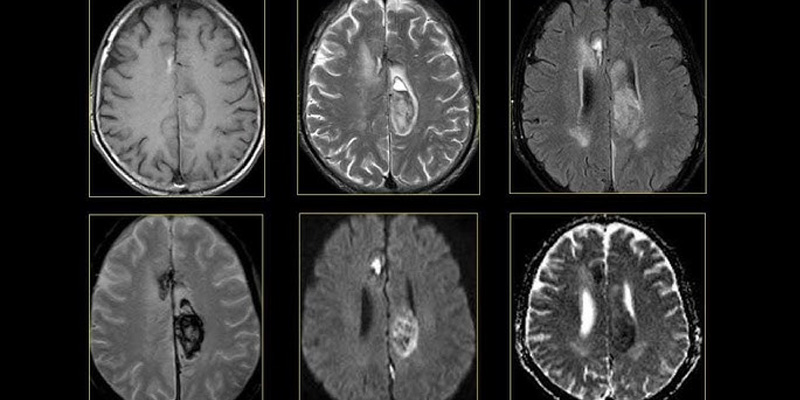

MRI não

MRI (Magnetic Resonance Imaging) được xem là tiêu chuẩn vàng trong đánh giá u não nhờ khả năng hiển thị chi tiết cấu trúc mô mềm, giúp bác sĩ nhận diện rõ:

- Kích thước và vị trí khối u

- Mức độ xâm lấn mô não

- Tình trạng phù não xung quanh

- Phân biệt u lành – u ác

- Xác định giới hạn để lập kế hoạch phẫu thuật

Ưu điểm là không dùng tia X, độ phân giải cao, hình ảnh chi tiết mạch máu và mô mềm và cho phép chụp nhiều chuỗi (T1, T2, FLAIR, DWI…) để phân tích u. Ngược lại, cũng có một số nhược điểm như thời gian chụp lâu (20–45 phút), không phù hợp cho bệnh nhân có thiết bị kim loại trong người và chi phí cao hơn CT.

Theo Mayo Clinic (2023): MRI có khả năng phát hiện nhiều dạng u não mà CT không thấy được, đặc biệt là u nhỏ hoặc u ở vùng khó như thân não.

MRI chẩn đoán ung thư não